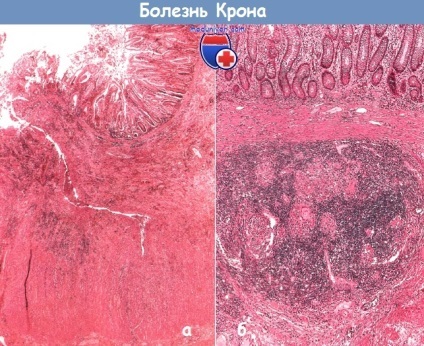

Anatomie patologica a bolii Crohn

In boala Crohn în procesul implică toate straturile peretelui intestinal, lumenul segmentului afectat ingusteaza peretelui intestinului îngroșat. Într-o realizare clasic, porțiunea de infestare a bolii 10-20 cm distal de ileon. In zonele afectate observate multiple stricturii de lungime variabilă, pe mucoasa - ulcere liniare cu edem submucos, ridicarea zonelor afectate ale membranei mucoase (imagine cu raze X „cobblestones“). stabili macroscopic un diagnostic de boala Crohn, în prezența alternanței zonelor afectate si neafectate ale intestinului sau prezența fistulelor intestinale.

Examinarea histologică facilitează detectarea pelete individuale (cel puțin 50% din porțiunea rezecat prevăzută o suprafață suficientă) cu fante ulcere, submucoasei fibroza si inflamatie transmural. În plus față de inflamarea mucoaselor, colecții individuale de limfocite trec prin peretele intestinului și apar în seroasa ca „granule inflamatorii.“ Macroscopice imagine - alternanța segmentelor de intestin afectate si neafectate; microscopice - modificări focale.

b - boala lui Crohn. Frotiuri perete submucosal ileon. Acumularea de granuloame necazeificat înconjurat de un infiltrat dens de limfocite

Nonsusceptibility tyromatosis granulom poate fi găsit oriunde în peretele intestinal. ulcere slit penetrează stratul submucoasei, și, uneori, întreaga grosime a mușchiului, care ar putea explica formarea de fistule. Cu toate acestea, există, de asemenea, o fuziune fibroasă de bucle intestinale cu altele. Stricturi in boala Crohn sunt rezultatul fibrozei submucoase, dublarea și placa musculare dezorganizare la nivelul mucoaselor. Alte exemple sunt date în capitolul 6. La pacienții cu sigmoidoscopia normală în prezența semnelor radiografice de leziuni ale intestinului subțire și descoperirile histologice caracteristice rectului încredere diagnosticarea bolii Crohn.

În cazul în care examenul histologic relevă granuloame, atunci probabilitatea de manifestari extra-intestinale sunt peste medie.